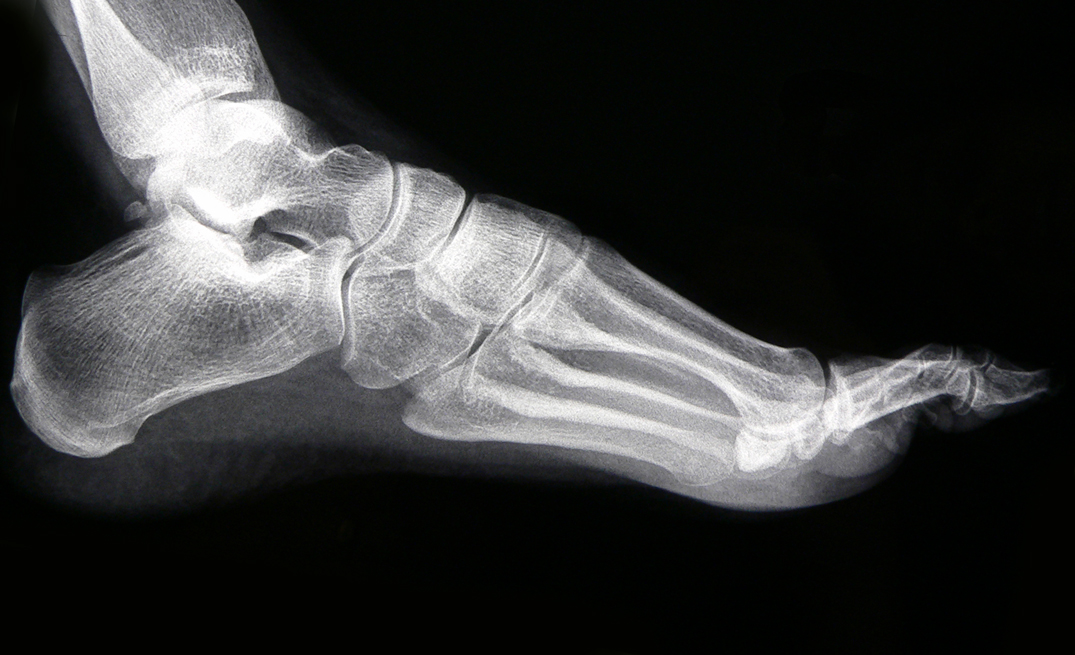

埃赛力达Omniblocks和X射线电源在一般放射线照相、数字放射线照相、断层扫描、血管/介入成像、图像引导放射疗法、放射肿瘤学和兽医学的医疗应用中产生X射线。